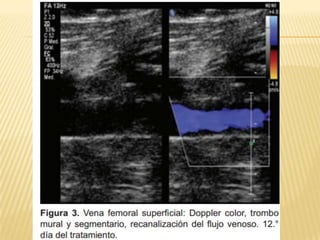

EVOLUCIÓN ECOGRÁFICA DE LA TROMBOSIS

VENOSA PROFUNDA EN PACIENTES CON

TROMBÓLISIS FARMACOLÓGICA

   Centro Médico ABC. The American British

Cowdray Medical Center IAP

   Anales de Radiología México 2010;2:76-

79. artíCulo original. Dr. José de Jesús

Rosas Sánchez, Dr. Miguel Ángel Ríos

Nava.